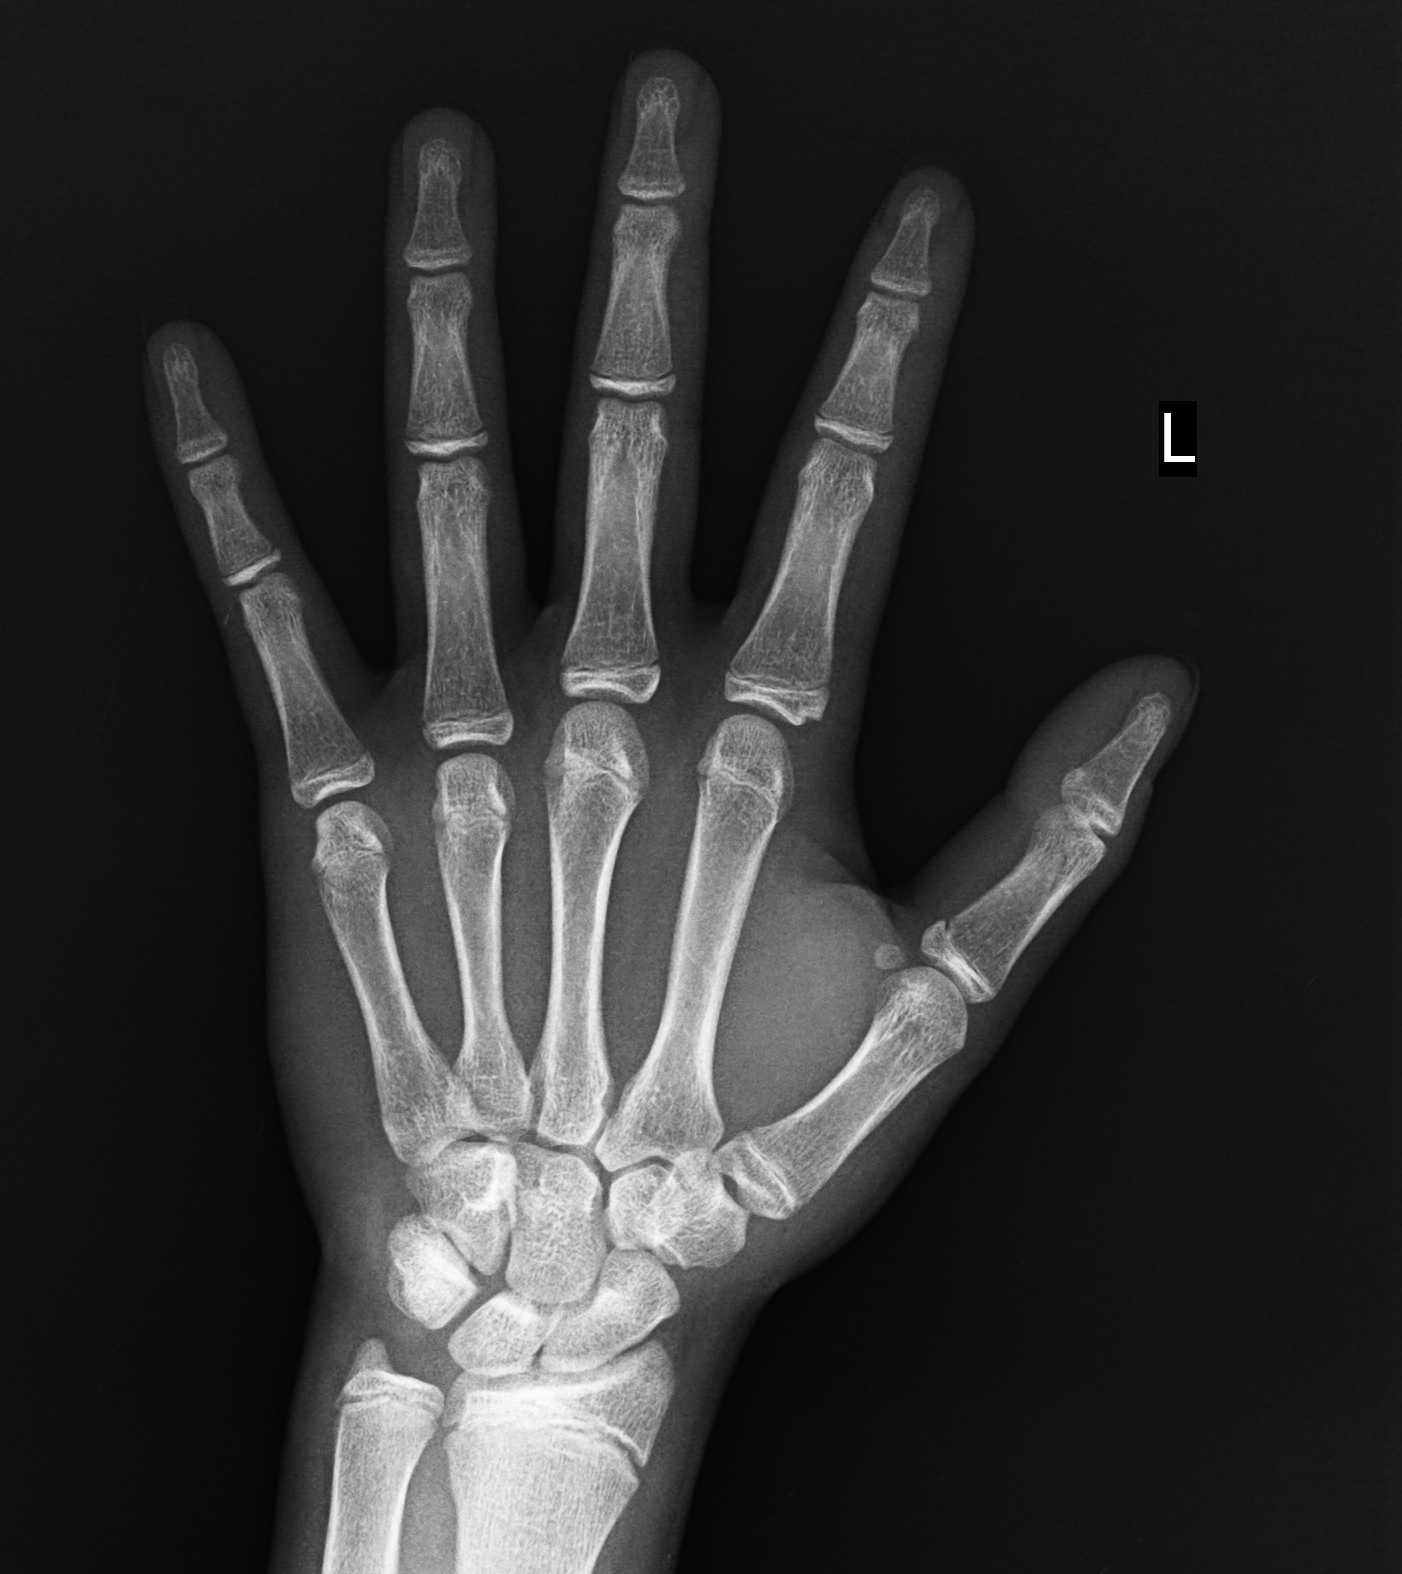

臨床圖片

wang zhi kun1104.15.1202.119.165.135.2021102806264460.1002.1